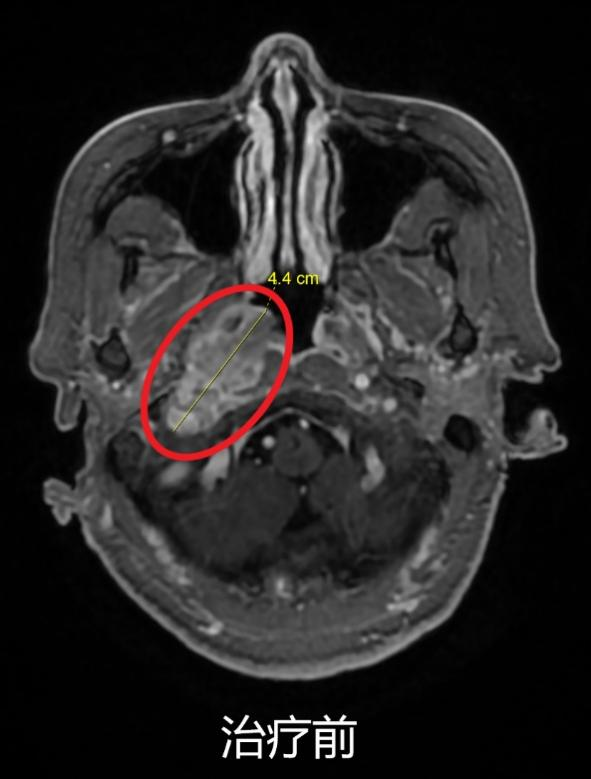

放射治療聯(lián)合免疫治療(肺癌伴腦轉(zhuǎn)移)